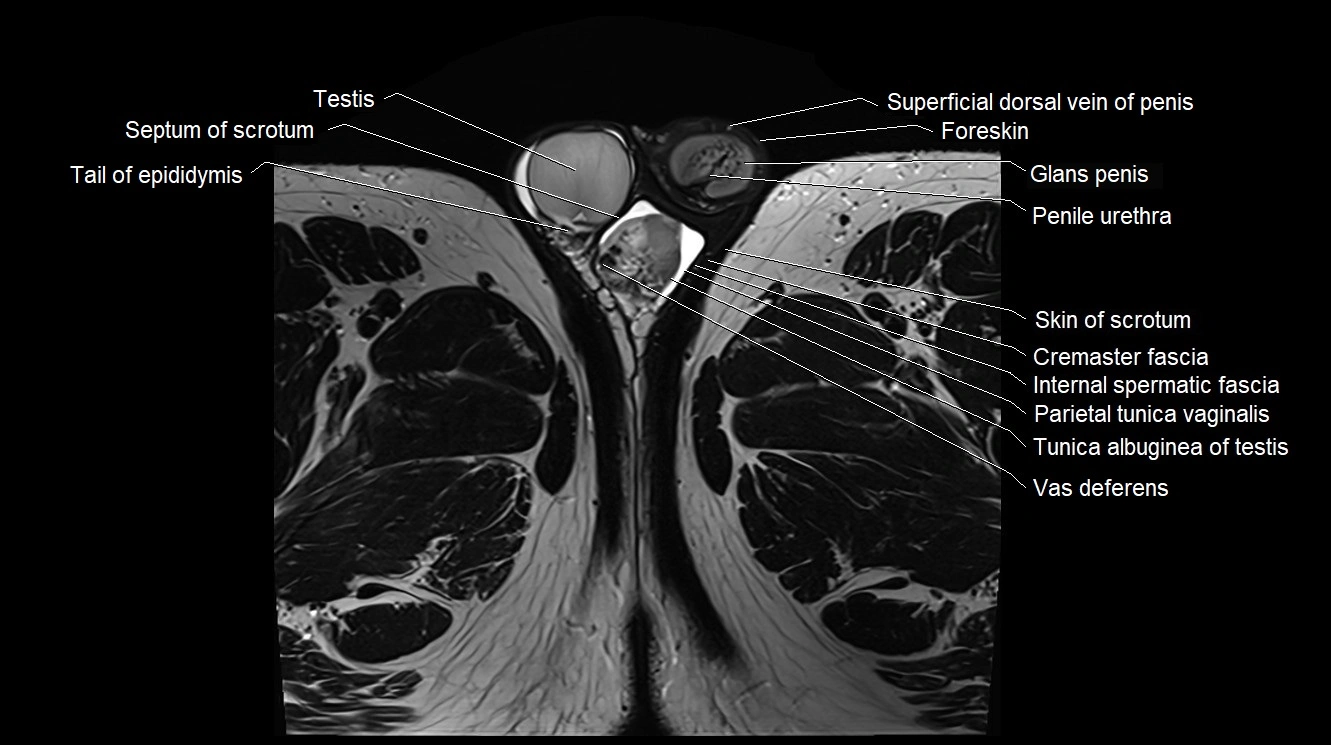

- Testis

- Septum of scrotum

- Tail of epididymis

- Cremaster fascia

- Internal spermatic fascia

- Parietal tunica vaginalis

- Tunica albuginea of testis

- Penile urethra

- Glans penis

- Foreskin

- Superficial dorsal vein of penis

- Vas deferens